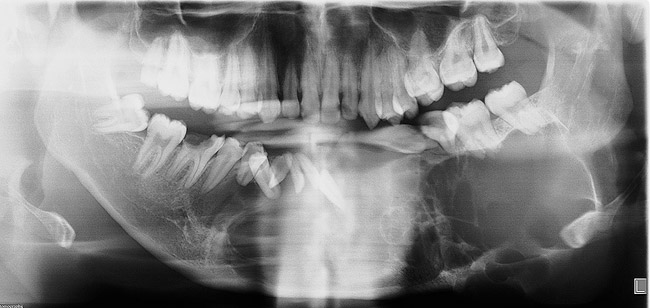

At that appointment, a cone-beam computed tomography (CBCT) scan and other radiographs were obtained. The radiographic findings revealed a multilocular expansile radiolucency that extended further than what was observed in the initial clinical examination. The radiolucency appeared to displace the inferior alveolar canal and lower border and had expanded but not perforated the mandibular cortex (Figure 3). The diagnostic work-up initially consisted of lesion aspiration. Then, multiple pieces were collected by incisional biopsy. The pathology report showed the histologic presence of epithelial islands that mimicked the enamel organ within a fibrous collagenized stroma. There were peripheral columnar cells resembling preameloblasts, a loose arrangement of epithelial cells with squamous metaplasia, and cystic degeneration toward the center (Figure 4). These histopathologic findings were consistent with the diagnosis of primary invasive ameloblastoma.4

Figure 3  Panoramic radiograph shows a multilocular radiolucency extending from the left second molar to the right first molar.

Figure 3